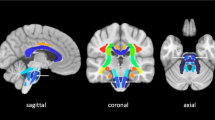

Figure 2 shows a threshold-free, cluster-enhanced, voxel-wise correlation map highlighting brain areas where MD was significantly greater (in red-yellow) or FA significantly lower (in green) (familywise error corrected p < 0.05 for both) in patients with poor versus good 6-month outcome, overlaid on the MNI152 1 mm brain atlas alongside a haemorrhagic lesion probability map (blue-white scale); an additional voxel-based analysis performed by swapping all affected hemispheres to the right side of the MNI152 brain is reported as supplementary material (Figure S1).

Threshold-free, cluster-enhanced, voxel-wise correlation map showing brain areas where MD was significantly greater (in red-yellow) or FA significantly lower (in green) (familywise error corrected p < 0.05 for both) in patients with poor versus good functional outcome, overlaid on the MNI152 1 mm brain atlas alongside a haemorrhagic lesion probability map (blue-white scale, range 5–20%)